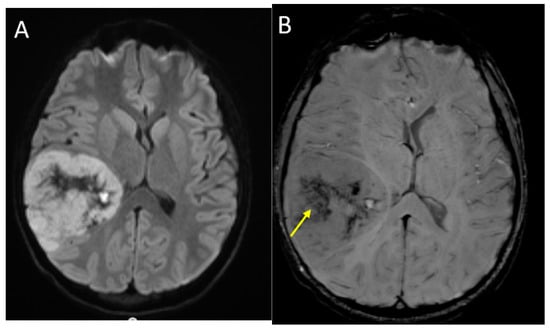

Supratentorial, non-midline, high-grade gliomas include H3 G34 mutant and H3 wild-type, and they are most commonly seen in adolescents [50]. On imaging, these usually present as large hemispheric and/or deep gray masses with a variable degree of heterogeneity, cyst formation, hemorrhage, and calcifications. On T2-weighted images, the solid components are iso- to mildly hyperintense, and there is surrounding vasogenic edema, mass effect, and often hydrocephalus. In contrast to pontine lesions, diffusion restriction is common in the solid components, reflecting the high cellularity and high nuclear-to-cytoplasmic ratio. Post-contrast enhancement is also common, although to a variable extent within the tumor. (Figure 7) Hemispheric high-grade gliomas share these imaging features with supratentorial embryonal tumors and ependymomas, and radiological distinctions between these entities may not be possible, although HGG are usually more often seen in older children than embryonal tumors [49,50].

Figure 7.

A 14-year-old male with H3 G34R mutant high-grade glioma. Axial DWI (A), axial SWI (B), axial T2 (C) and coronal post-contrast T1-weighted (D) images demonstrate a large mass in the right parieto-temporal lobes, with diffusion restriction of the solid portions, central areas of blood products and/or mineralization (arrow), isointense T2 signal with central necrosis (curved arrow), and heterogenous post-contrast enhancement.